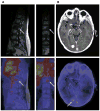

Increased human epidermal growth factor receptor 2 (HER2) expression is a hallmark of aggressive breast cancer. Imaging modalities have the potential to diagnose HER2-positive breast cancer and detect distant metastases. The heterogeneity of HER2 expression between primary and metastatic disease sites limits the value of tumor biopsies. Molecular imaging is a noninvasive tool to assess HER2-positive primary lesions and metastases. Radiolabeled antibodies, antibody fragments, and affibody molecules devise a reliable and quantitative method for detecting HER2-positive cancer using PET. HER2-targeted PET imaging is a valuable clinical tool with respect to both the care and maintenance of patients with breast cancer.